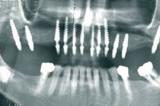

Существует классика жанра – имплантация, при которой врач сначала разрезает десну, затем откидывает ее лоскут для того, чтобы видеть кость, проводит установку имплантата и зашивает...